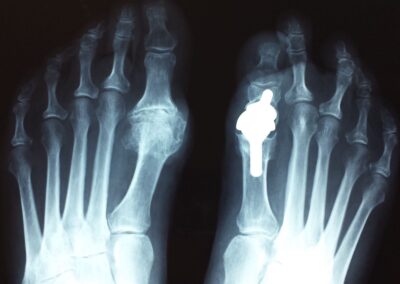

Alluce valgo

E’ frequente specie nelle donne e prevede, quando indicato, un trattamento chirurgico. E’ importante considerare univocamente anche le patologie eventualmente associate dell’avampiede e del retropiede per una corretta indicazione chirurgica. Lo studio clinico poi deve essere integrato da una radiografia dei piedi in comparativa e sotto carico gravitario.

Le tecniche chirurgiche a nostra disposizione sono molteplici e vanno individualizzate sul paziente. Tra le varie preferisco la osteotomia distale del primo metatarso fissata con adeguati mezzi di sintesi preferibilmente in titanio associata al rilascio della capsula sul versante laterale. In alcuni casi difficili può essere indicato associare anche una osteotomia della prima falange dell’alluce oltre a trattamenti diretti alla correzione di eventuali griffe digitali associate.

Il problema della chirurgia riparativa dell’ alluce valgo è la recidiva della deformità che addirittura è meno grave della ipercorrezione con conseguente alluce varo secondario. Occorre dunque programmare le osteotomie eventualmente associate alla testa del primo metatarso ed alla base della prima falange con un accurato planning preoperatorio in base a parametri morfologici da ricercare in una radiografia preoperatoria eseguita sotto carico gravitario.E’ fondamentale associare un riequilibrio delle parti molli capsulari e tendinee che andranno opportunemente adattate alla nuova configurazione geometrica dell’avampiede.Sarà poi importante l’ausilio di bendaggi o taping nelle prime settimane postoperatorie a mantenere la correzione ottenuta fino alla completa guarigione delle correzioni ossee e delle parti molli.Preciso che è fondamentale seguire l’evoluzione della cicatrizzazione con controlli ogni due settimane nei primi 45gg postoperatori con possibilità di correggere con adeguati taping eventuali iper piuttosto che ipo correzioni.